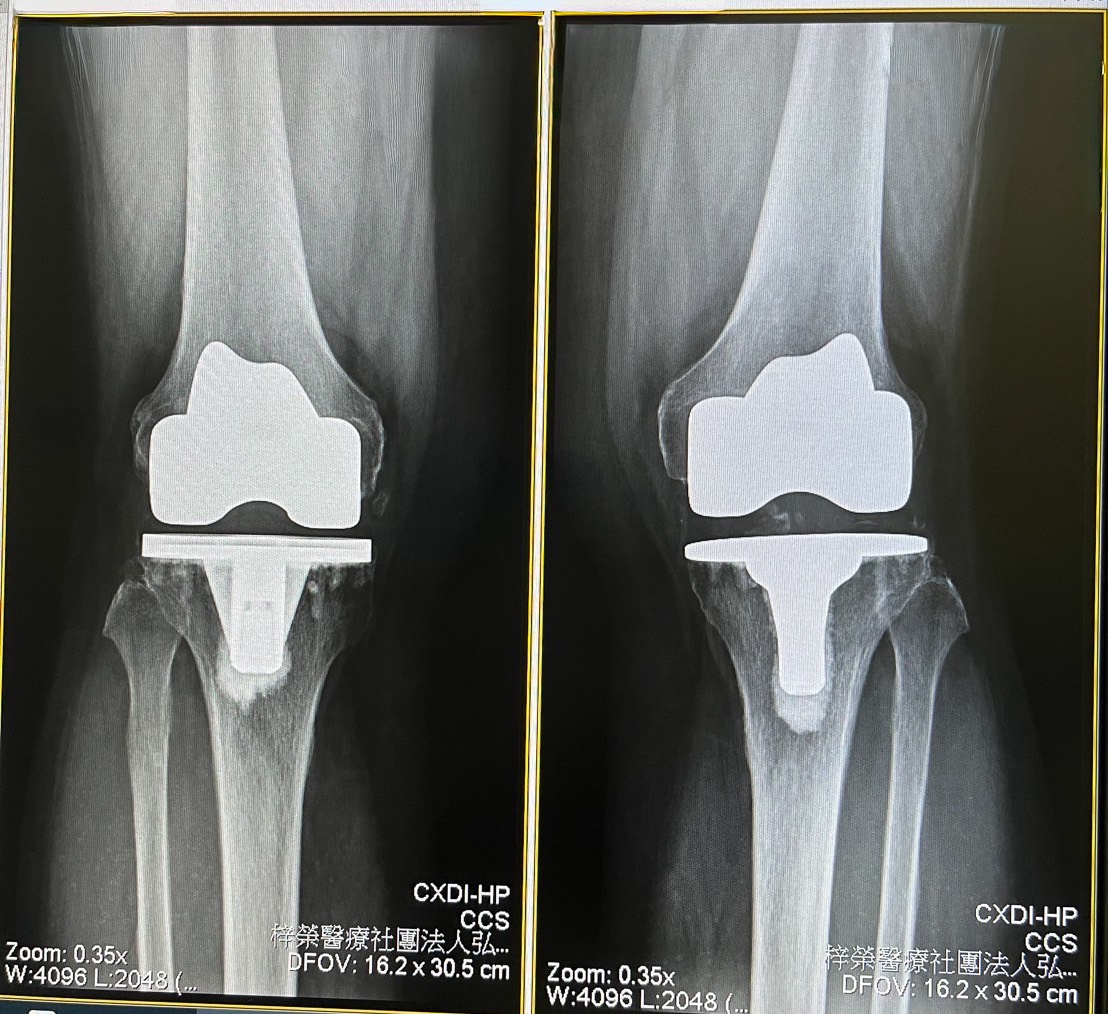

手術完成後,患者於隔日即可下床步行,膝關節的疼痛大幅減輕,步行時的不適幾乎完全消失。手術後五至六天,她甚至能夠自行上下樓梯,生活品質明顯提升。

圖3. 左側髖關節置換術後